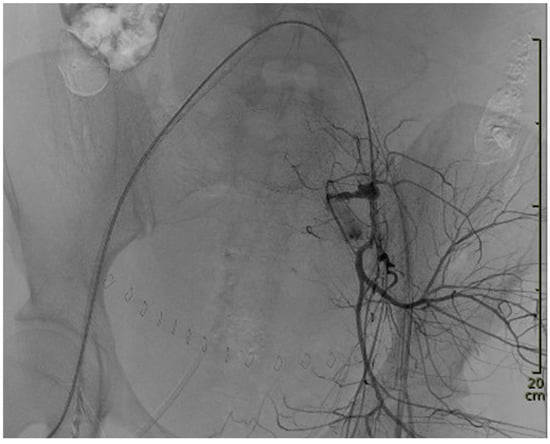

Bleeding localization and embolization from a super-selective position in the left uterine artery were started within seven minutes after the angiography had commenced. For bleeding localization, the REBOA balloon was unblocked intermittently. The initial bleeding control at the site of laceration was achieved using detachable coils. To prevent sustained bleeding from possibly injured smaller vessels (not visible on the angiogram) and from the contralateral side, and to ensure vessel occlusion in a patient in severe hemorrhagic shock and consecutive deficiency coagulopathy, microspheres and gelfoam were applied in addition. Bleeding control was finally achieved using eight detachable Concerto™ coils (Medtronic, Minneapolis, MN, USA), Embozene™ Microspheres for Embolization (700 µm) (Boston Scientific, Marlborough, MA, USA), and gel foam. Hemostasis was achieved through the successful embolization of both uterine arteries, as shown in Figure 2.

Figure 2. Final angiography after embolization.